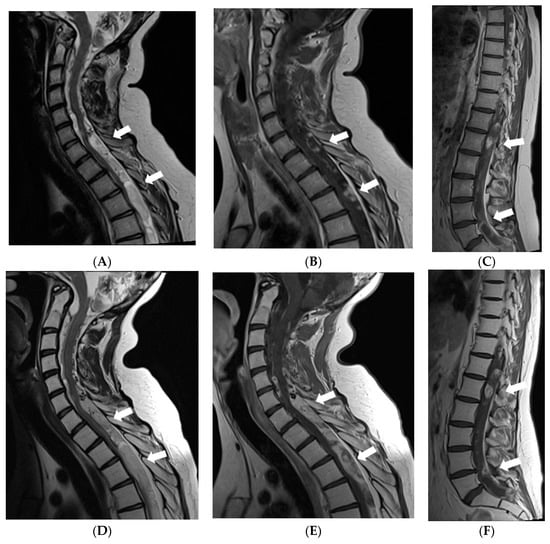

Figure 5.

MRI of the spinal cord 6 years after the onset of symptoms: (A,D) Sagittal T2W, (B,E) T1W postcontrast images of the cervical and the upper thoracic spine, (C,F) postcontrast images of the middle/lower thoracic and the lumbar spine. In May 2017, (A–C) multiple confluent cystic extramedullary masses were found in the spinal canal through all its length, compressing the spinal cord at the level from C6 to T9 vertebrae. There was some nodular contrast-enhancement in the tumourous masses and diffuse meningeal enhancement. After radiotherapy in December 2017 follow-up MRI (D–F) demonstrated enlargement of the extramedullary masses in the lower cervical-upper thoracic spine with more vivid and diffuse enhancement, also, more vivid diffuse meningeal enhancement.